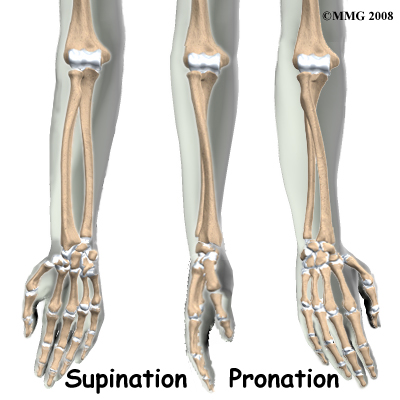

There are two bones in the forearm. The ulna is a straight thin bone that goes from the elbow to the wrist and forms the axis of rotation of the forearm. The radius is thin at one end becoming thicker and stronger towards the wrist. It is slightly bowed to allow it to rotate around the ulna when the forearm is rotated. To demonstrate this, place your forearm flat on a table in front of you with the palm up and the back of the little finger touching the table. Now roll the hand over until it is positioned palm down on the table. Note that the little finger and the elbow are still in nearly the same position while the thumb has moved from outside to inside. When the forearm rotates, the little finger side where the ulna is forms the axis (spindle) around which the rest of the forearm rotates. We can see that the radius is on the outside of the forearm when it is rolled outwards but crosses over the ulna when the forearm is rotated in. The radius is bowed to allow this movement to occur. If the bowing is not accurately restored after a fracture the forearm will not rotate correctly and this would limit some important functions of the hand.